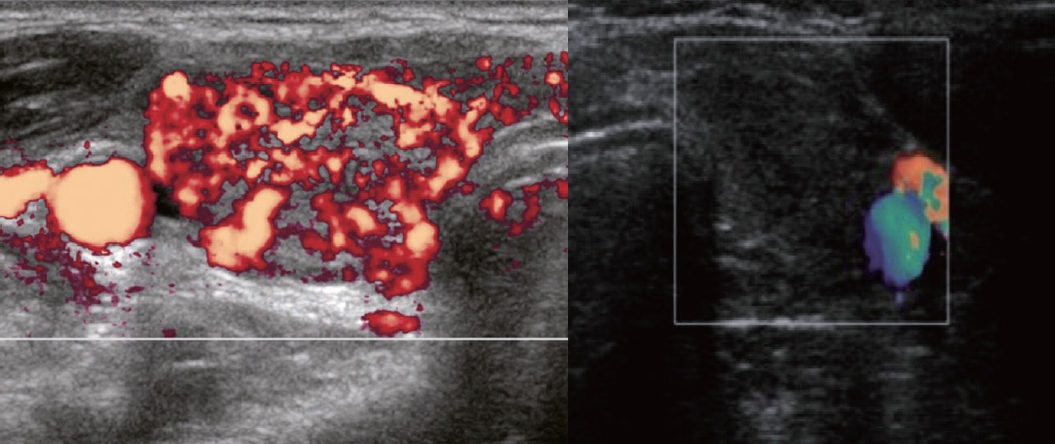

최근 초음파 기기의 활용이 증가하면서 갑상선기능항진증의 진단에 초음파가 널리 사용되고 있으며 일부 국외 진료지침에서는 그레이브스병의 진단 시 초음파 검사를 권장하고 있다[7]. 정상 갑상선에서는 혈류가 주로 주요 갑상선 혈관과 그 분지에 국한되며 실질 내 동맥 혈류는 관찰되지 않는다. 반면 그레이브스병이나 하시중독증(hashitoxicosis)과 같은 병적 상태에서는 실질 내 혈류가 현저히 증가한다. 그레이브스병의 경우 초음파에서 갑상선이 미만성으로 비대해지고 실질이 저 에코를 보이며 혈관 분포 및 혈류 속도가 증가된 특징을 보인다. 이에 비해 무통갑상선염은 초음파에서 대부분 혈류 증가가 관찰되지 않는다(Fig. 2). 하지만 무통갑상선염에서도 혈류 증가가 관찰되기도 하고 검사 및 검사자 간 차이도 존재하므로 임상 소견 및 혈청학적 검사를 고려하여 종합적으로 해석해야 한다[8,9]. 일부 연구에서는 그레이브스병 환자에서 superior thyroid artery의 peak systolic velocity가 정상 또는 무통갑상선염 환자보다 유의하게 높다고 보고하였다[10]. 일반적으로 40-60 cm/s를 임계값으로 제시하며 이 기준은 민감도 85%, 특이도 93%로 높은 진단 정확도를 보인다[10]. 따라서 혈류 분포 및 혈류 속도 증가는 무통갑상선염, 아급성 갑상선염, 약물 유발 갑상선중독증 등 다른 원인과의 감별에 유용하다. 아급성 갑상선염의 경우 갑상선초음파에서 갑상선 크기는 정상이거나 약간 커져 있으며 전체적 또는 국소적으로 불규칙한 저에코 병변이 관찰된다. 저에코 부위는 대개 통증 부위와 일치하며 도플러 초음파에서는 갑상선중독기 동안 혈류가 감소된 소견을 보인다. 회복된 후에는 초음파 소견도 정상화된다.

Figure 2.

Ultrasonographic findings of Graves’ disease and painless thyroiditis. Comparison of ultrasonographic findings between Graves’ disease (left) and painless thyroiditis (right). In Graves’ disease, diffuse increased vascularity throughout the thyroid parenchyma produces the characteristic pattern known as thyroid inferno, whereas in painless thyroiditis, vascularity is absent or only minimally increased.